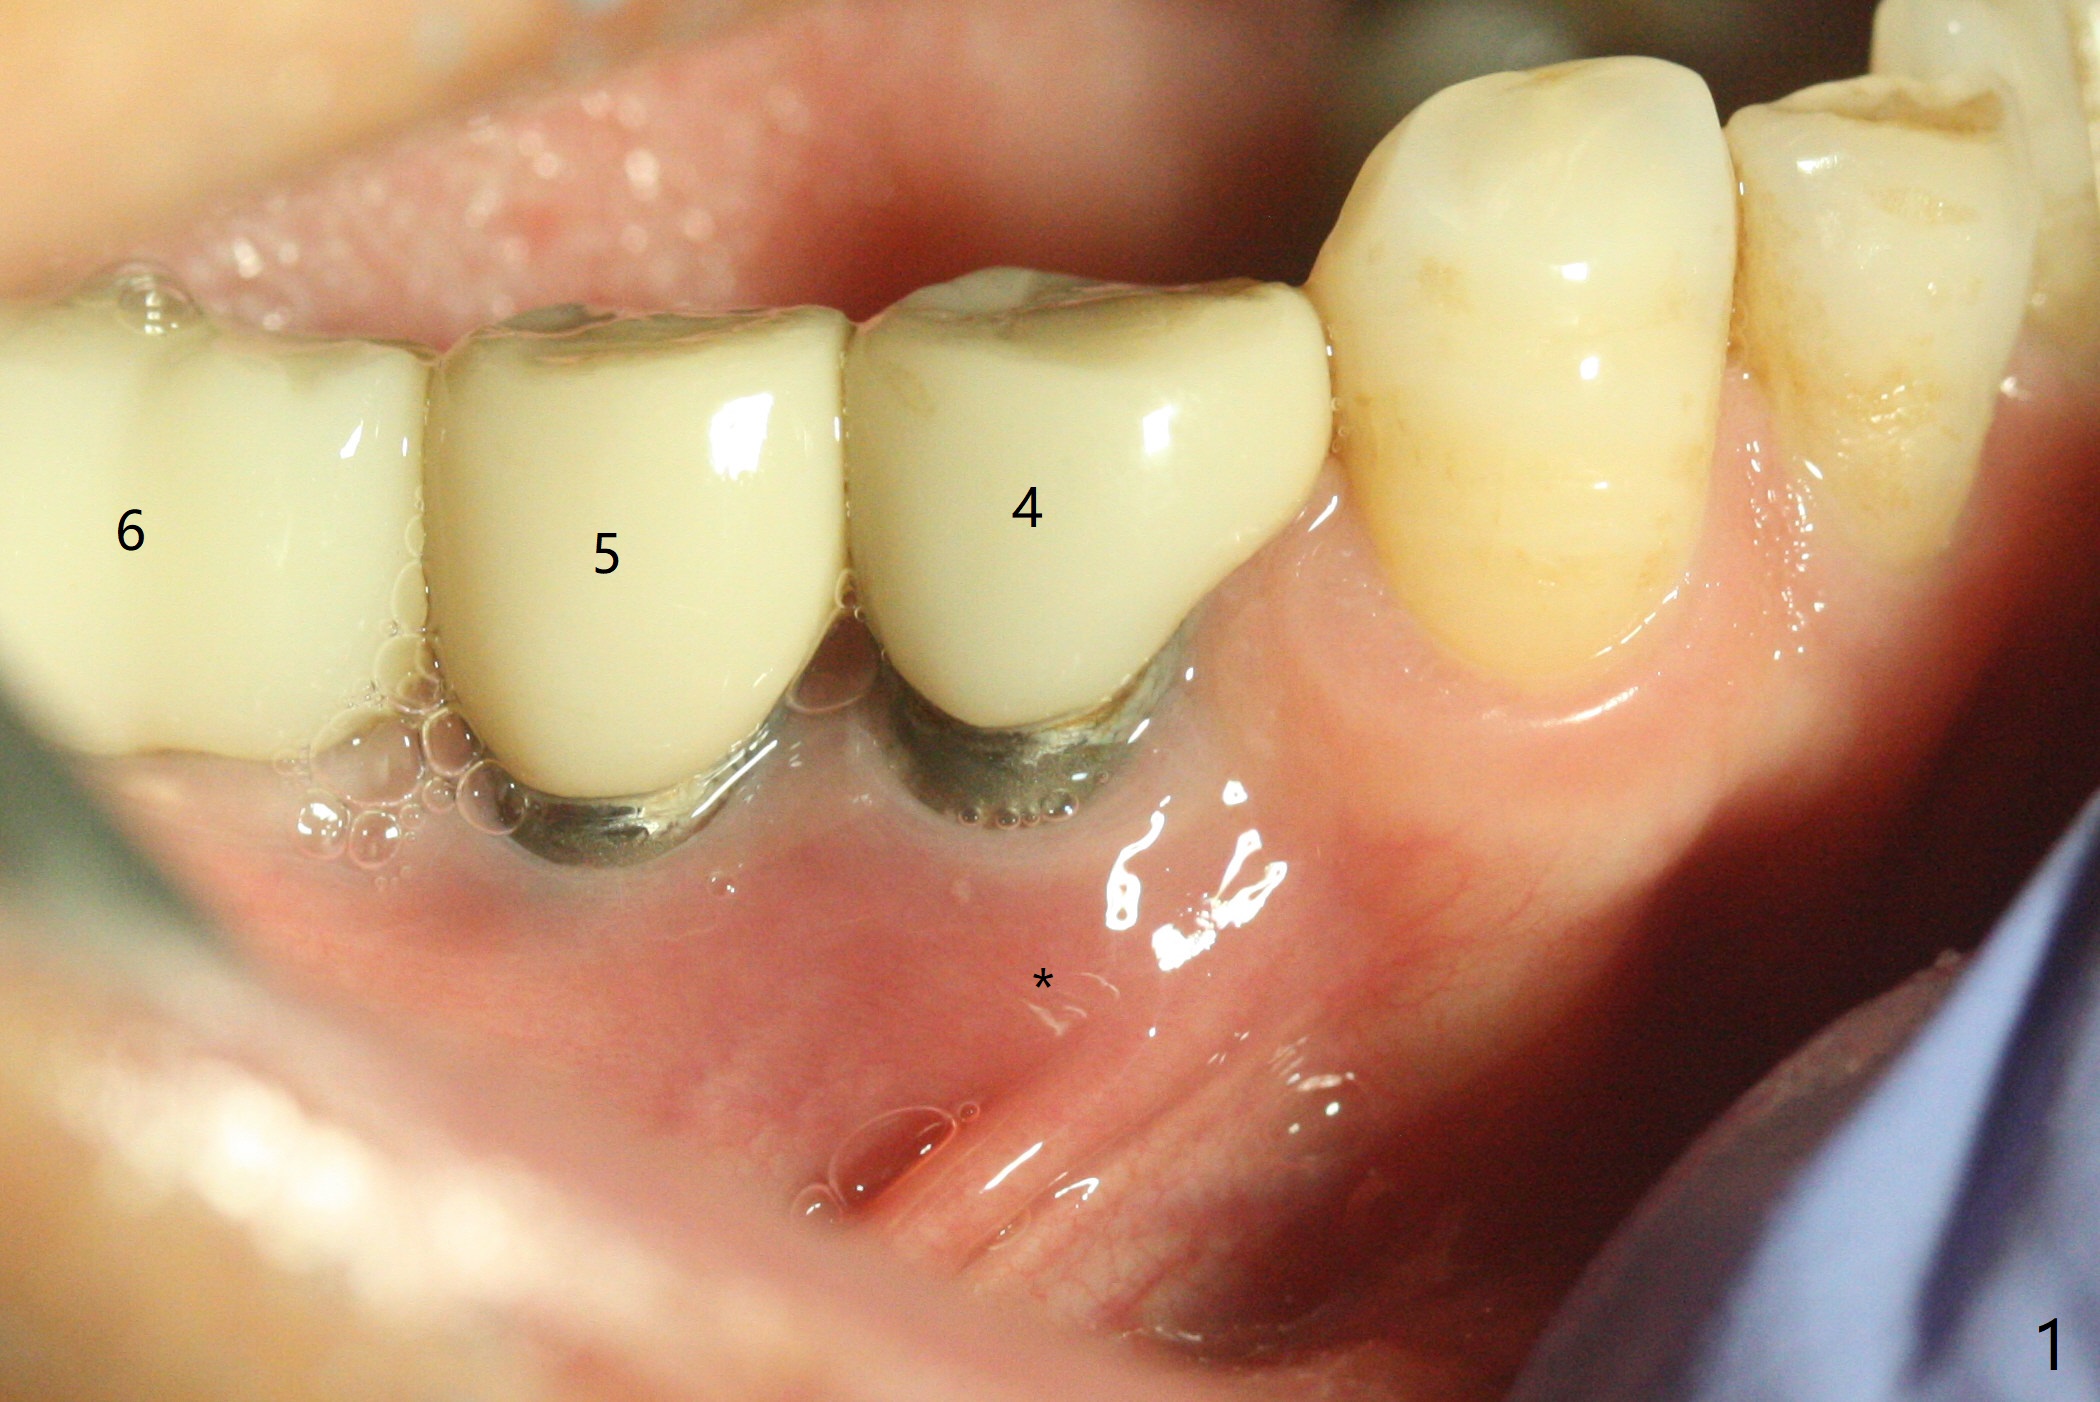

61岁女右下4(粘固后5.5年)植体周围炎(颊侧牙龈没有角化龈(图一:*)),因为颊侧种植(图二),翻瓣证实(图三),取出4.5毫米两段式植体,在舌侧骨质(图四:L)即刻植入2.5毫米一段式植体(图五),颊侧缺损植入大量粘性骨粉(图六:*),覆盖PRF膜后,缝合(图七),与图二对比,窄植体明显舌侧移位。术后一个月撤除牙周敷料(图八),并没有马上制作临时牙冠,让病人容易搞好局部卫生,促进伤口愈合(图九),术后三个月塞入龈线(图十:^),制备基台,植体在牙槽嵴中性位置(颊舌侧),但愿颊侧有足够再生骨质,覆盖植体螺纹。